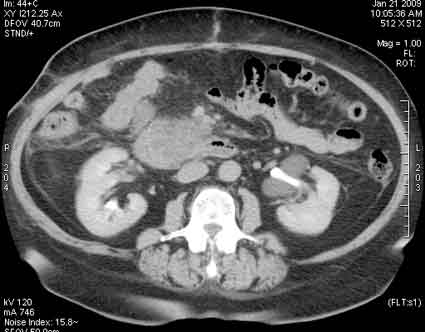

3D-реконструкция

4web.jpg (11.29 КБ) 1230 просмотров